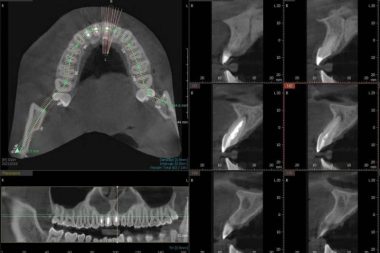

El innovador CBCT dental 3D que realiza la Clínica Blay+Monzó